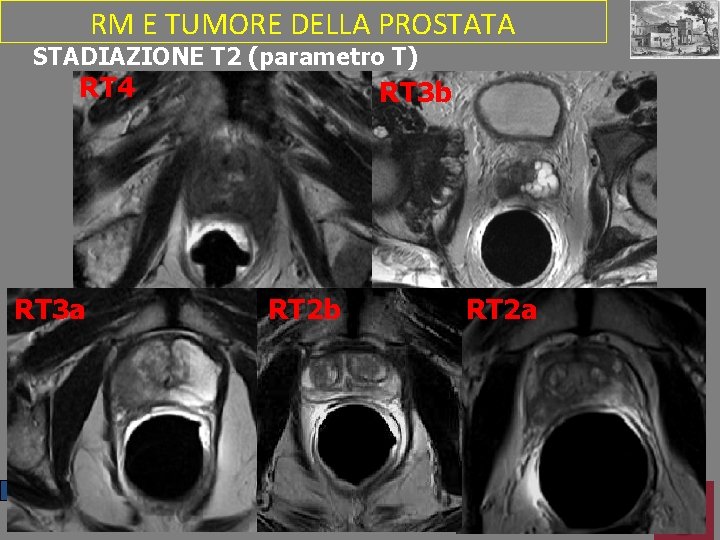

RM E TUMORE DELLA PROSTATA STADIAZIONE T 2 (parametro T) RT 4 RT 3 a RT 4 RT 3 b RT 2 a